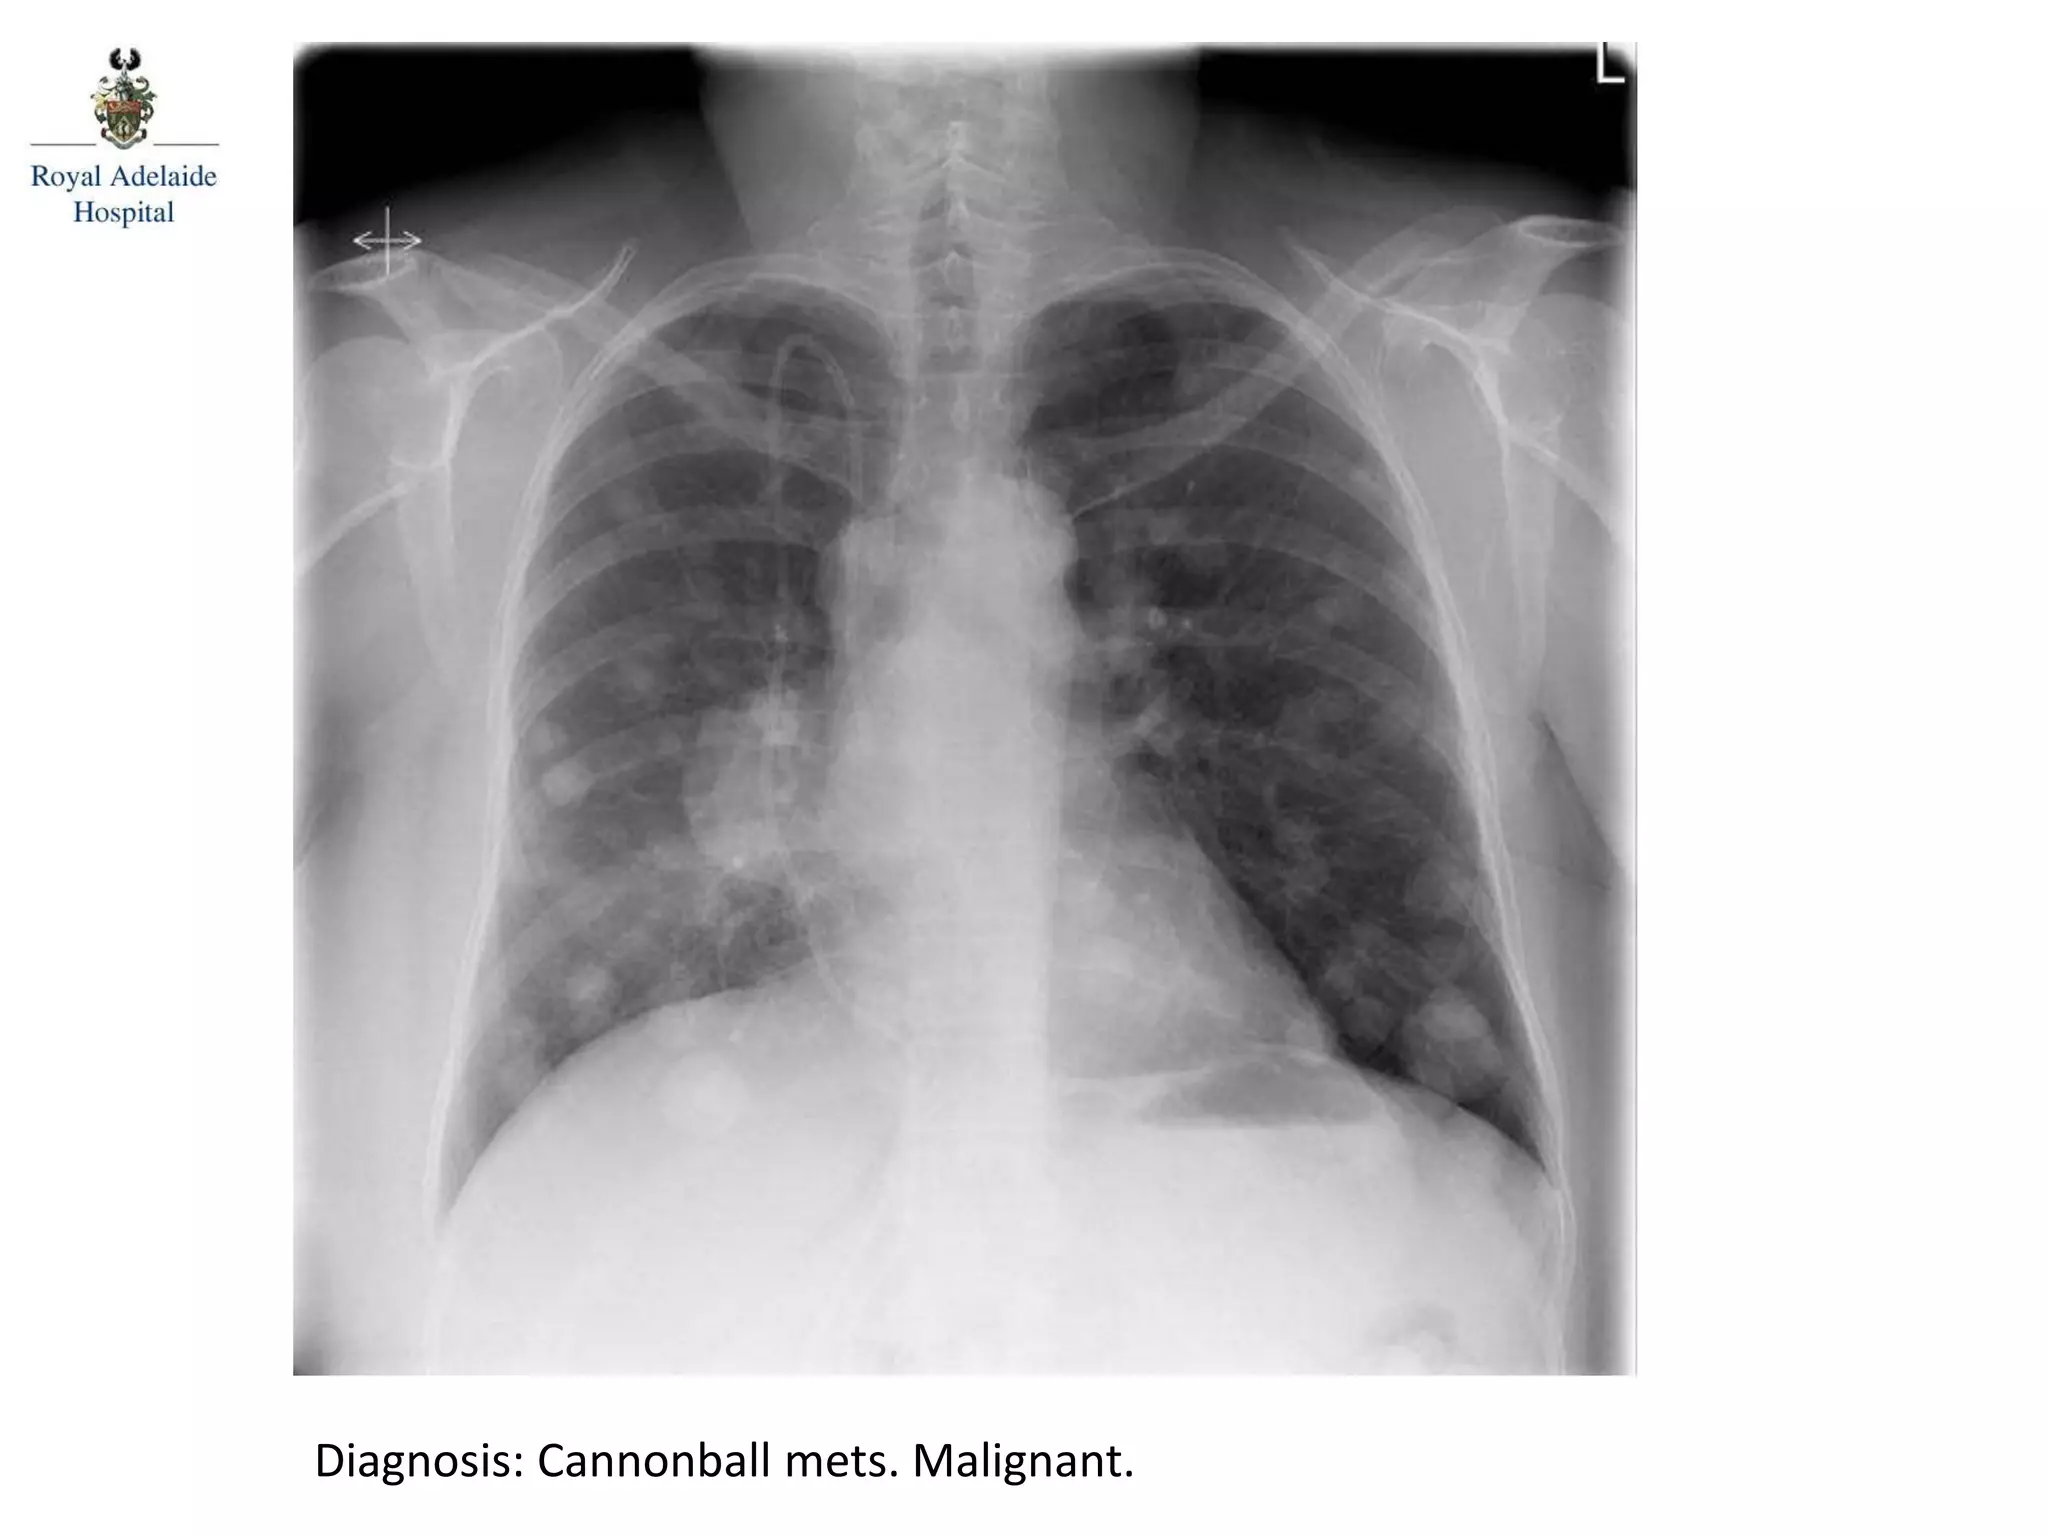

Diagnosis: Cannonball mets. Malignant.